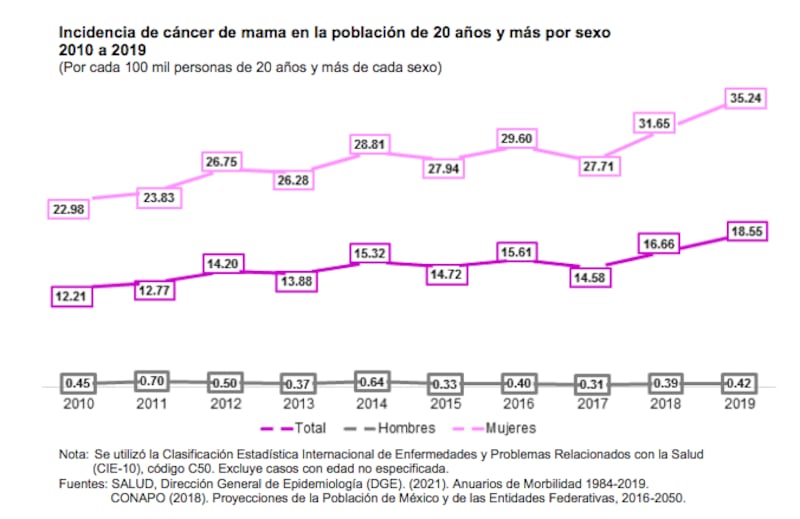

Te recomendamos: Se duplicó en 10 años la incidencia de cáncer de mama, hay pacientes desde 15 años